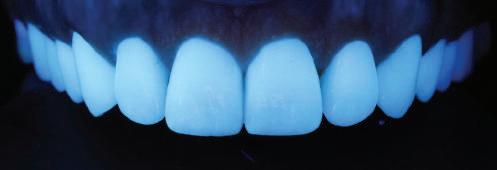

Препарираните зъби бяха импорти рани в Exocad и насложени върху ес тествените форми от биометричния дизайн, като така стана ясно дали зъ бите са били препарирани коректно. По този начин зъболекарят и зъботехни кът работят в една и съща екосистема и резултатът е оптимален. С короната се справихме чрез диги тална редукция на циркония в Exocad, като по този начин на практика създа дохме циркониево кепе, след което про изведохме фасета от IPS Empress Cad Multi. Кепето от Katana Zirconia на зъб 12 с букално послойно нанесена керами ка бе фрезовано (послойното нанасяне бе направено, за да се подобри връзката и да се осигури адхезивно циментиране на фасетата към циркониевото кепе, както и за да се напасне цветът към този на съседните зъби). При първото сканиране регистрирах ме цялата горна зъбна дъга, така че, ко гато се наложи да сканираме повторно, бе изтрит и сканиран наново само зъб 12, тъй като венците не бяха отдръп нати при второто сканиране.

Една седмица след препарацията на зъбите и циментирането на цирко ниевото кепе бяха изработени 12 IPS Empress Cad Multi фасети. Макро- и микротекстурата на фасе тите бяха направени на ръка, след кое то бяха нанесени 3D характеризации с боички, а полирането отново бе напра вено ръчно, за да им се придаде естест вен и естетичен вид. Предизвикателството тук беше короната да има същите оптични характеристики като тези на остана лите зъби при естествена светлина, през поляризационен и флуоресцентен филтър. 3D принтерът бе Fromlabs, софтуерът за фрезоване – Mill Box, а фрез апаратът –imes icore CORiTEC 350i. В крайна сметка постигнахме ес тествен вид на усмивката с натурал на зъбна морфология при изцяло диги тален протокол, при който дизайнът бе направен първоначално и през всич ки етапи на лечението се придържахме към него до самия край Излишно е да отбелязваме, че всички сме удовлетворени от постигнатото! Преди След Победител в категория „Клиничен случай с изцяло дигитален протокол“ в конкурса „Усмивка на годината 2022“

планта бе поставена временна коронка (фиг. 10 и 11), докато бъде изготвена окончателна та. Бе постигнат отличен кра ен резултат. Меките тъка ни около импланта напълно заздравяха, което доприне се за перфектната хармония между бяла и розова естетика (фиг. 12–15).